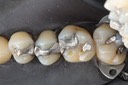

Gary Umeda #3 amalgam removal